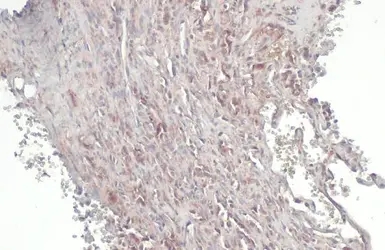

RIP3 antibody detects RIP3 protein at cytoplasm and nucleus by immunohistochemical analysis.

Sample: Paraffin-embedded human lung cancer.

RIP3 stained by RIP3 antibody (GTX131188) diluted at 1:500.

Antigen Retrieval: Citrate buffer, pH 6.0, 15 min